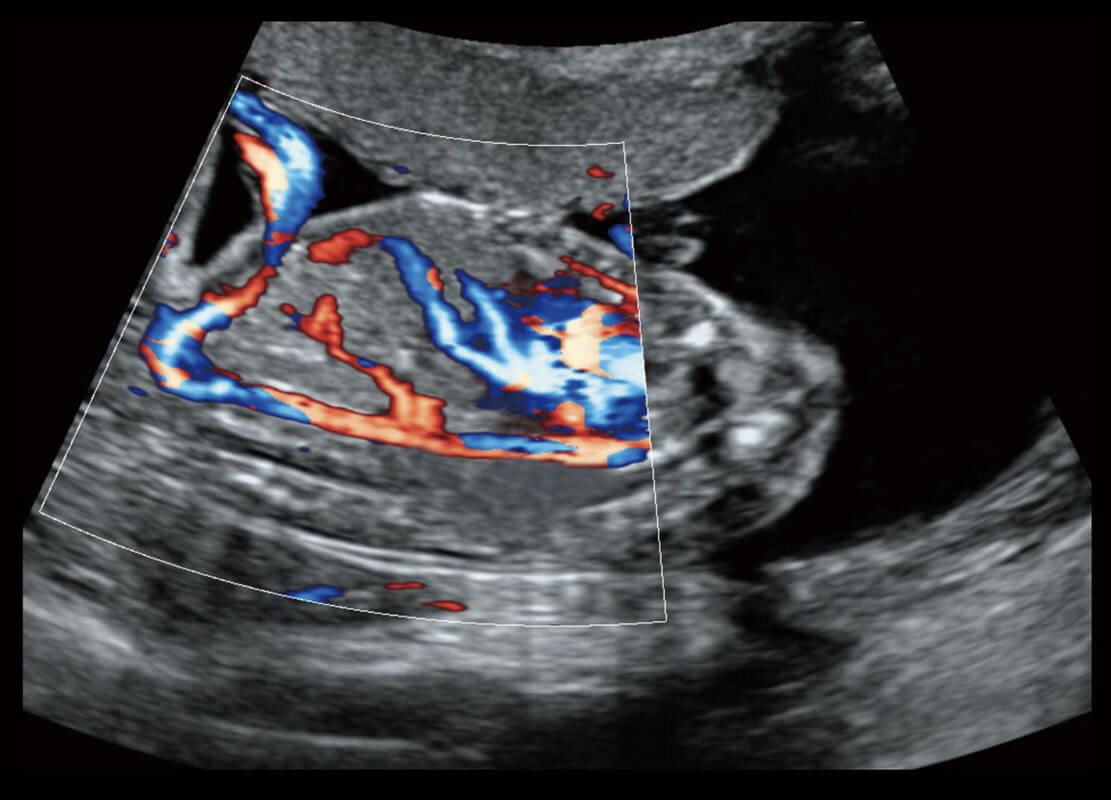

P60搭載寬頻帶線(xiàn)陣探頭、寬景成像、彈性成像技術(shù),為您提供乳腺應(yīng)用方案。P60支持高頻相控陣探頭、線(xiàn)陣探頭、腹部高頻探頭、腹部微凸探頭等,豐富的探頭群搭載敏感的彩色血流成像,適用于新生兒多種臟器檢測(cè)要求,滿(mǎn)足新生兒篩查需求。

新生兒肝血管癌

新生兒脊髓圓錐

新生兒心臟